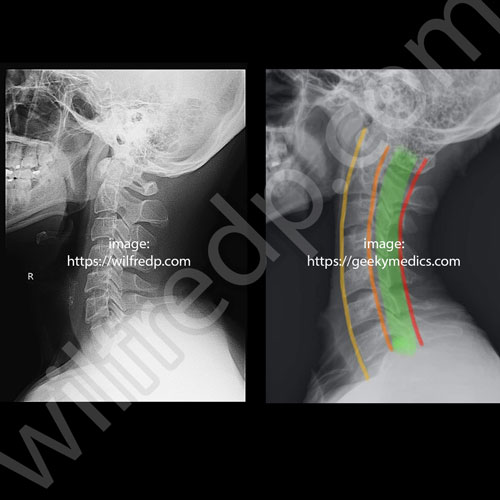

從X光圖可以看到,我的頸部已經不是正常的彎曲像個C的形狀(附上的對比圖),已經成了一個直綫。而且正拍我的脖子好像偏左,但我好奇的點在X光報告裏,所有的觀察都寫著 Normal。基於我是看診后才發現的,我也就沒多追究了。